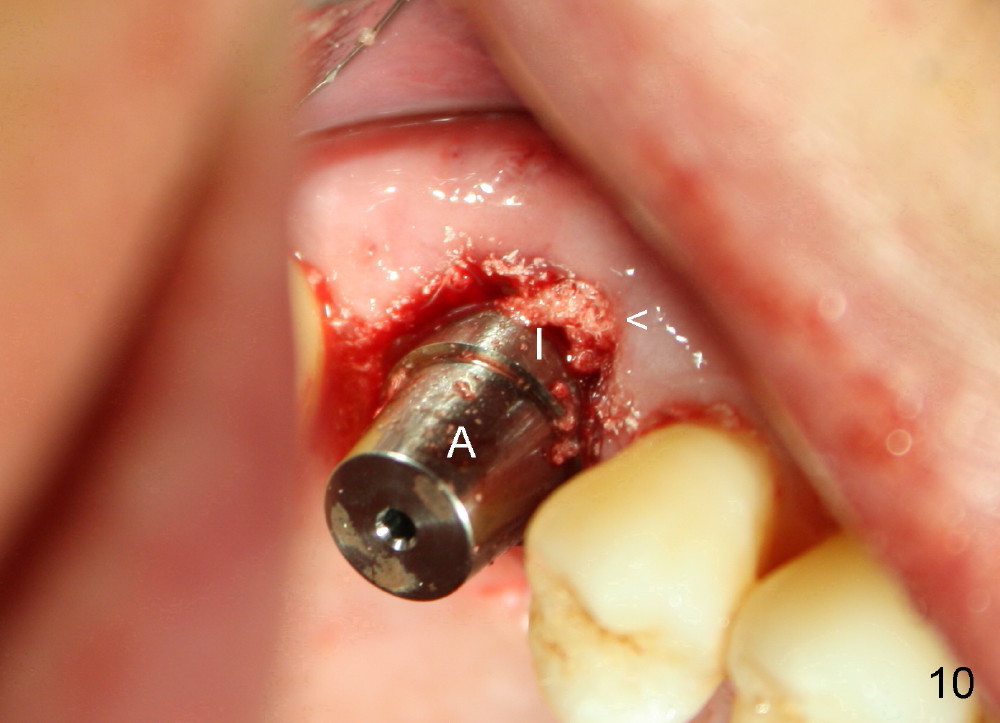

The upper right 1st molar of a 48-year-old man has severe perio endo disease (Fig.1 #3); the bone height for immediate implant (Fig.2) is about 3.5 mm (Fig.1 vertical line). There is a buccal (Fig.3 B) abscess (*); the palatal (Fig.4 P) root is exposed. After extraction, the socket available for immediate implant (Fig.5,6 S) is buccal (without septum), whereas the apex of the palatal root is far away from the main socket. In fact there is an advantage: the socket is smaller. Osteotomy is created in the main socket as palatal as possible, using osteotomes, reamers and taps (Fig.7 T). The sinus floor is lifted (Fig.7 ^). When 7x17 mm implant is placed (Fig.8 I), the insertion torque is >60 Ncm. The remaining socket (Fig.8 *) is to be packed with mixture of autogenous bone, allograft and synthetic bone (Osteogen) (Fig.9,10 <). Immediate insertion of an abutment (Fig.8-10 A) helps retain perio dressing (Fig.11,12). No collagen membrane is used in this case to cover the bone graft before placement of perio dressing. Postop the patient cannot tolerate oral Amoxicillin because of stomach upset. The dose is reduced. Two weeks postop, the perio dressing is stable, but discolors (Fig.13). When the dressing is removed, the buccal bone graft is exposed, which is not abnormal. What is unusual is discoloration (Fig.14). The significance of the latter is not revealed until 3 months postop when the patient remains asymptomatic, but there is an apical fistula (Fig.15 <). There is a communication between the fistula and the buccal sulcus of the implant: water passing freely. Based on the position of the buccal plate of the neighboring teeth (*), the buccal plate of the implant should be lost, which is consistent with finding of PA (Fig.16, as compared to Fig.8). Guided bone regeneration seems necessary.